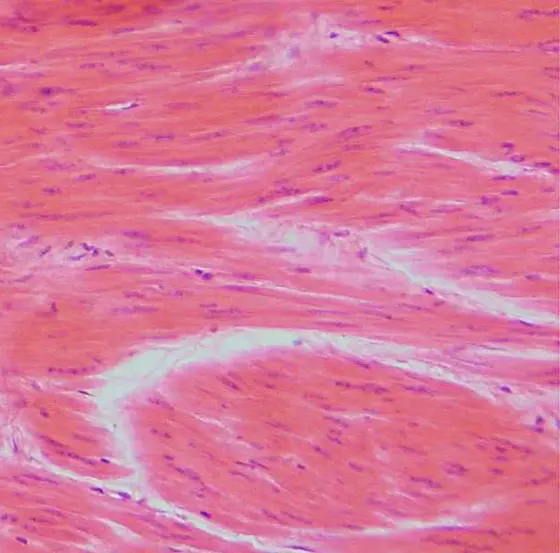

Leiomyosarcoma is a cancer of the smooth muscles

Leiomyosarcoma is a type of cancer of the smooth muscles that can arise almost anywhere in the body. Common places are the uterus, the abdomen or the muscles of the blood vessels. Even the tiny muscles that make our hair stand on end can be affected.